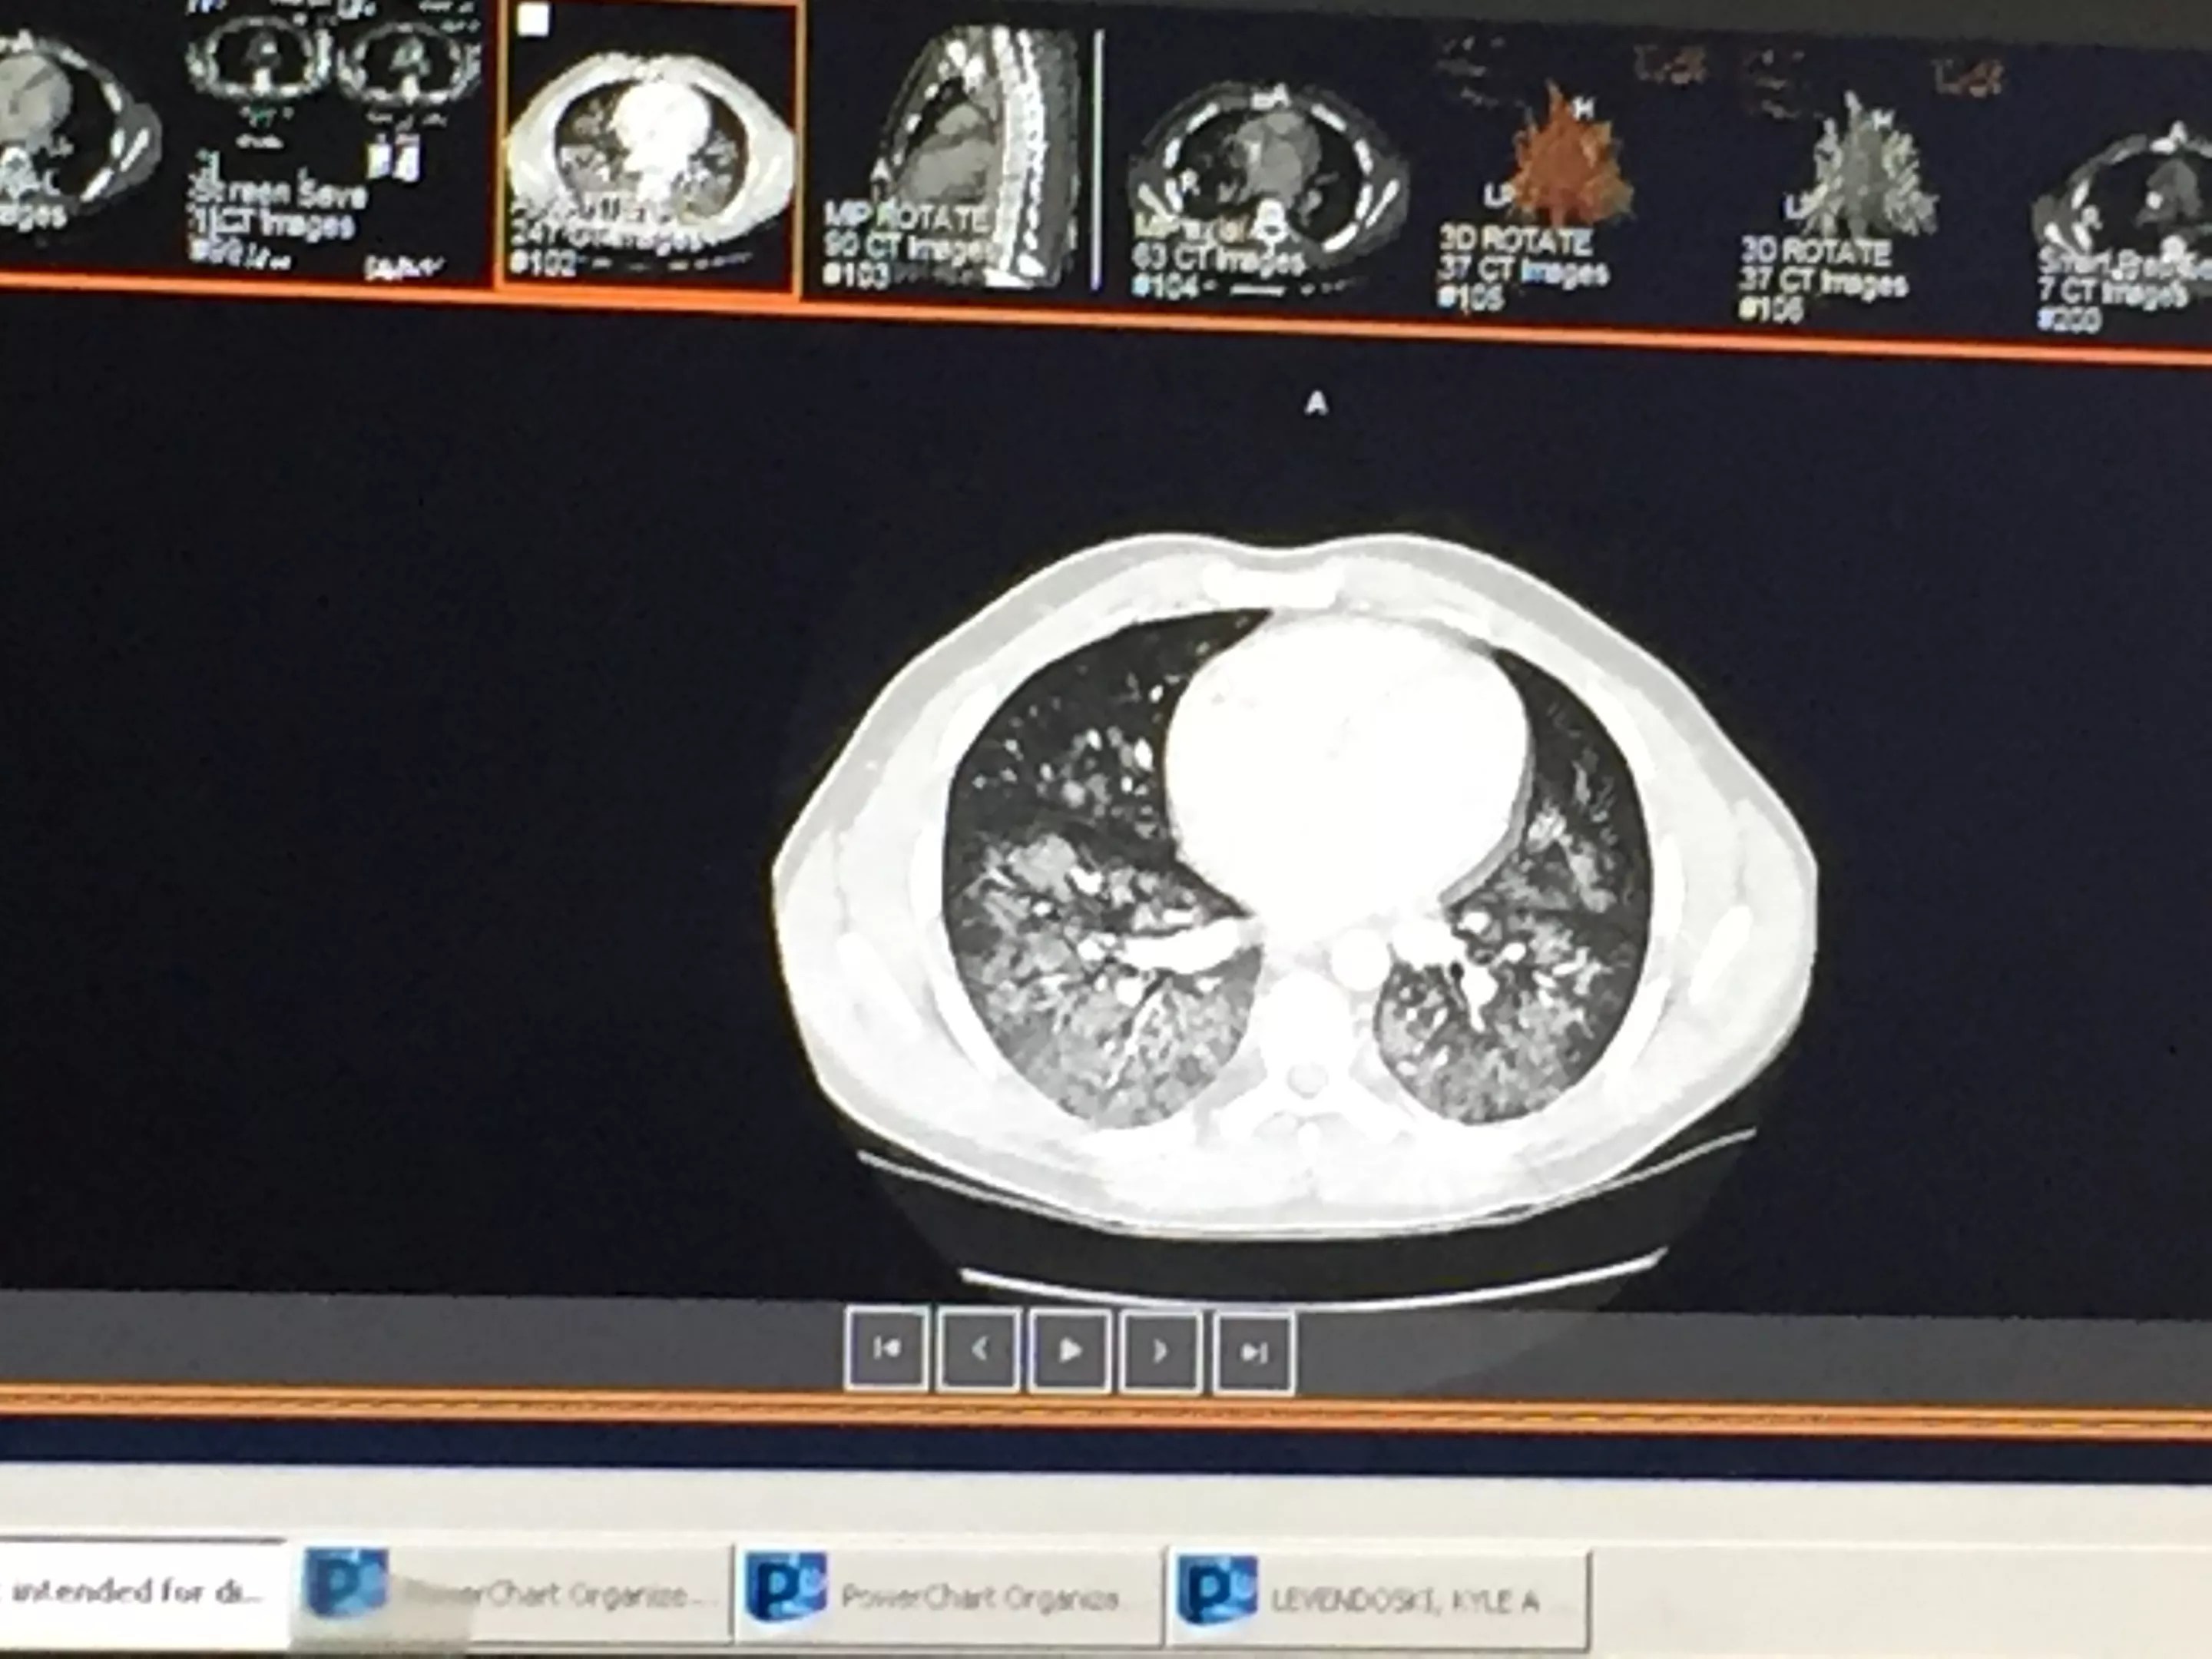

After his violent vomiting incident on September 4, he was taken to Abrazo Scottsdale Campus hospital and immediately put on oxygen therapy, which wasn’t stopped until he left on Saturday. After undergoing testing that included MRI and CT scans, he was diagnosed with a type of pneumonia caused by chemicals.

From his hospital bed, Levendoski watched news footage of others who had come down with similar pulmonary illnesses. He began comparing the images of those patients’ lungs with his own. “I looked on my phone to see how my lungs looked and how theirs looked. Mine looked worse!”